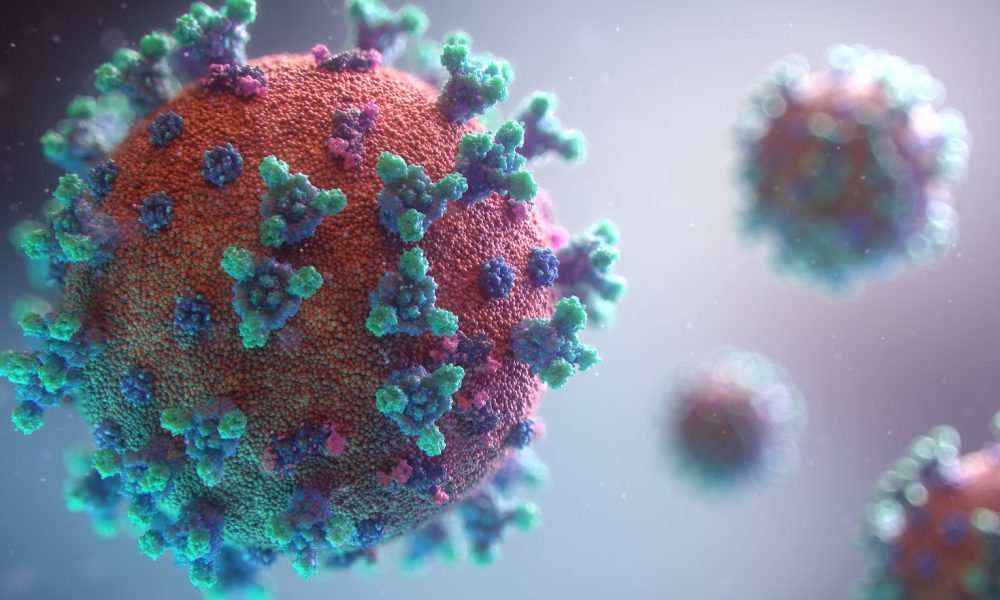

MANILA – About 43 percent of recorded deaths due to the coronavirus disease 2019 (Covid-19) are unvaccinated emphasizing the crucial role of vaccination in preventing the...

When the World Health Organization formally declared an end to the COVID-19 pandemic’s designation as a Public Health Emergency of International Concern (PHEIC), it may seem...

COVID vaccines are very effective, but for some groups they don’t generate as strong an immune response. These groups include older adults and people with weakened...